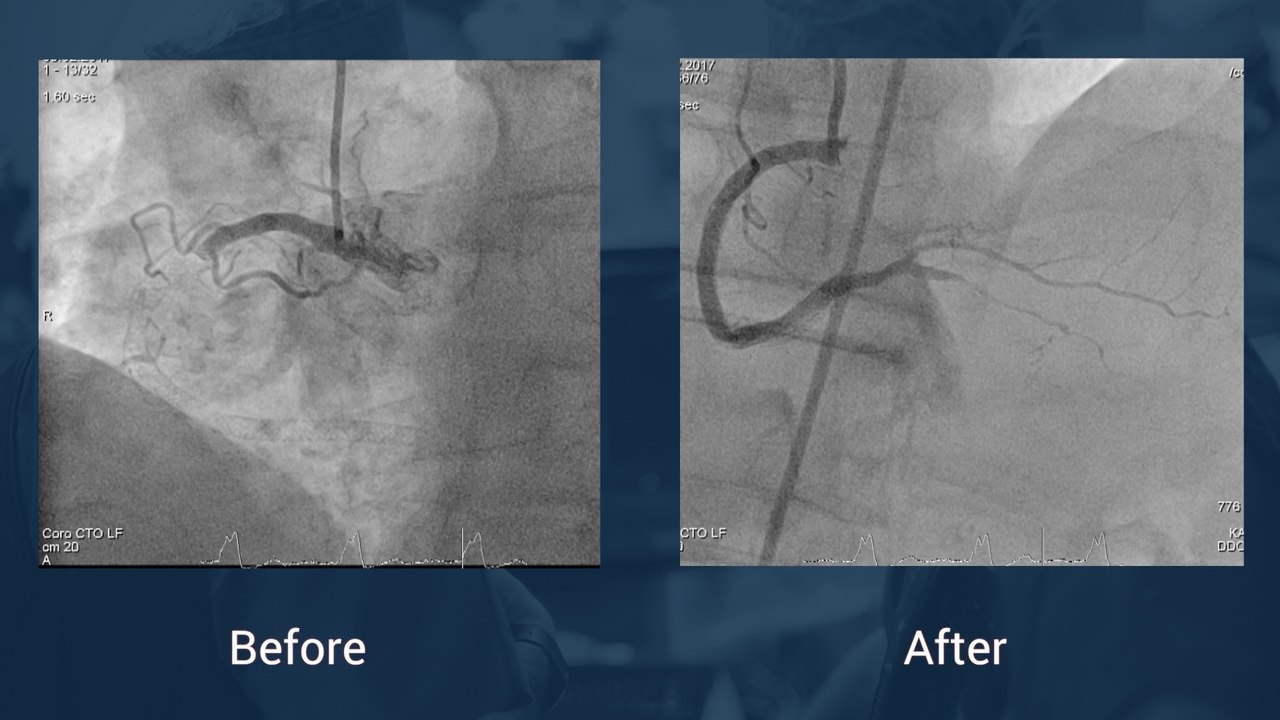

•PCI OM1  + failed attempt revascularisation CTO RAC (06/2016)

•Today 2nd attempt at CTO RAC

•Antegrade dissection rentry (ADR) technique

•CrossBoss /Stingray